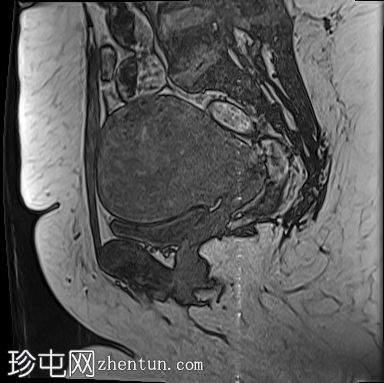

轴位

T2加权像

子宫前倾且体积增大,交界区呈边界不清、弥漫性对称性增厚。T2加权像和T2脂肪抑制像均显示条纹状高信号,无异常强化或扩散受限。

子宫内膜腔、交界区和外层肌层边界不清。

MRI上,T2加权像上交界区增厚超过12 mm是子宫腺肌症的特征性表现。